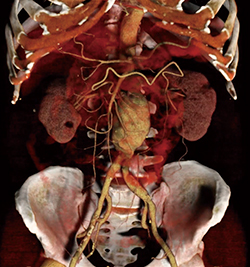

横町:最も衝撃を受けたのは,新たな画像表示法の“レンブラント”です。従来のZiostation2は,筋肉や筋腱などの整形領域で表示が難しい場合がありましたが,レンブラントは視認性が向上し,実際の手術視野に近い画像が表示されるため,非常に有用だと思います。また,ユーザーインターフェイスが大きく変更されていて,すっきりした印象を受けました。

井田:レンブラントはハンドリングも悪くなさそうですね。これまで見たかぎりでは,血管より表面の軟部組織で有用ではないかと感じました。小川さんはいかがですか。

小川:Ziostation2を長年使用していたので,ユーザーインターフェイスが大幅に変わったことで,当初は慣れないこともありました。ただ,“レンブラント”や“トランスペアレンシー”などの新機能により,体表では今まで以上に深い表現の画像が提供できるのではないかと思います。腹部血管などは影がよりリアルに見えるため,それが外科の医師にどのような印象を与えるかは今後詳細な検討が必要だと思いますが,表現や設定を細かく変更できるので,有用性があると思います。

坂部:作成できるボリューム数が増えたほか,患者選択などの際に2つのワークフローを展開できるなど,細かな工夫がされていますよね。特に心臓血管外科では,術前に医師が3DWSで計測を行うため,技師だけではなく医師が簡単に操作できるのは良いと思います。また,IVR支援画像で椎体と血管を見せたい場合は骨を透かしたりしていたのですが,レンブラントにより,そのような処理をせずともわかりやすい画像が作れるのではないかという印象を持ちました。